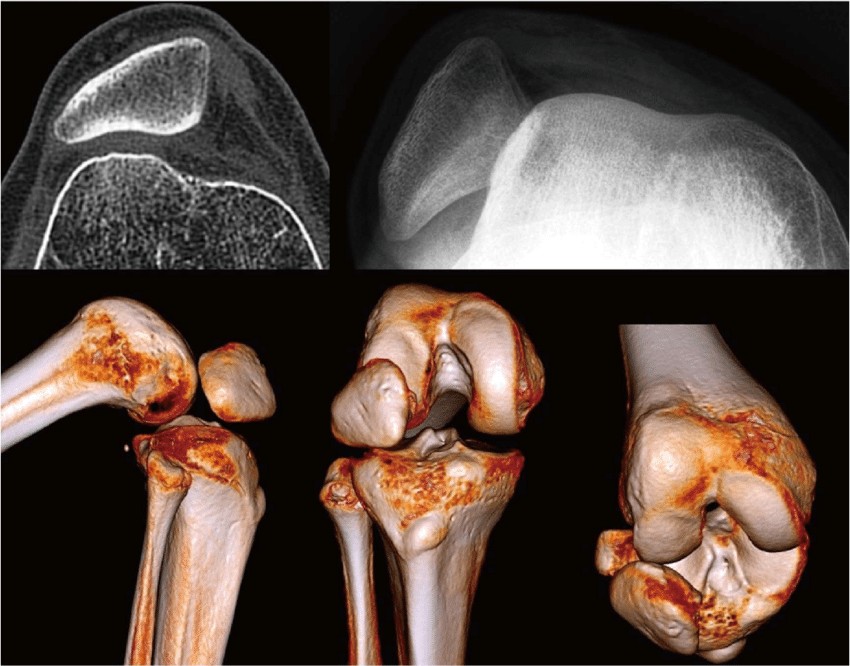

-Рентген коленного сустава для поиска свободных частиц кости и неправильного положения коленной чашечки.

Ваш врач может диагностировать нестабильность надколенника, задав вам вопросы о вашем колене и просмотрев вашу историю болезни. Врач также может осмотреть ваше колено и попросить вас двигать им в различных диапазонах движений. Это поможет вашему врачу проверить силу мышц вокруг колена и оценить, насколько хорошо работают связки, удерживающие коленную чашечку на месте. Визуализирующие обследования, такие как рентген, МРТ или сканирование костей, могут помочь выявить любые проблемы с костями или мягкими тканями внутри или вокруг колена.